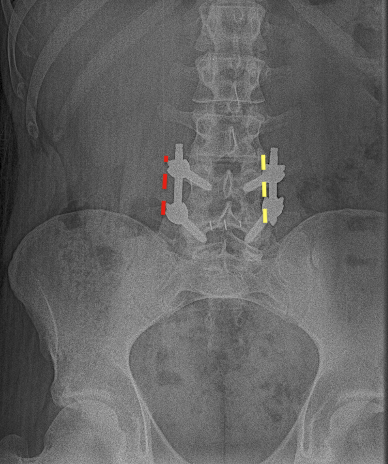

En el TLIF MIS (Transforaminal Lumbar Interbody Fusion Minimal Invasive Surgery) se obtiene el mismo resultado que el TLIF clásico o abierto, con la diferencia que sólo se realizan dos incisiones paramedianas y no se separa la musculatura de sus anclajes osteoligamentosos. El postoperatorio es mucho mejor en el TLIF MIS que en una cirugía abierta, sin embargo muchas veces no se puede plantear TLIF MIS y hay que realizar TLIF «abierto», sobre todo en patología degenerativa avanzada cuando vamos a asociarlo con otras técnicas (Laminectomía lumbar o artrectomía bilateral para corrección de lordosis o listesis).

La Fijación transfacetaria lumbar puede usarse como técnica de fusión MIS en la Discectomía lumbar, asociando un injerto intersomático. También puede tener su utilidad como complemento del TLIF MIS en el lado percutáneo. La orientación, tamaño e integridad de las facetas así como la ausencia de subluxación limita, en mi opinión, un uso más generalizado de esta técnica.

La escoliosis degenerativa requiere a menudo de abordajes extensos para fusionar muchos niveles. El postoperatorio de estos pacientes es arduo y no exento de complicaciones. La técnica de XLIF (OLIF) aplicada en esta patología en dos o tres niveles permite una fusión adecuada que puede combinarse con una instrumentación posterior percutánea +/- una descompresión selectiva microscópica a través de pequeñas incisiones con poca pérdida de sangre y escaso daño a la musculatura posterior.